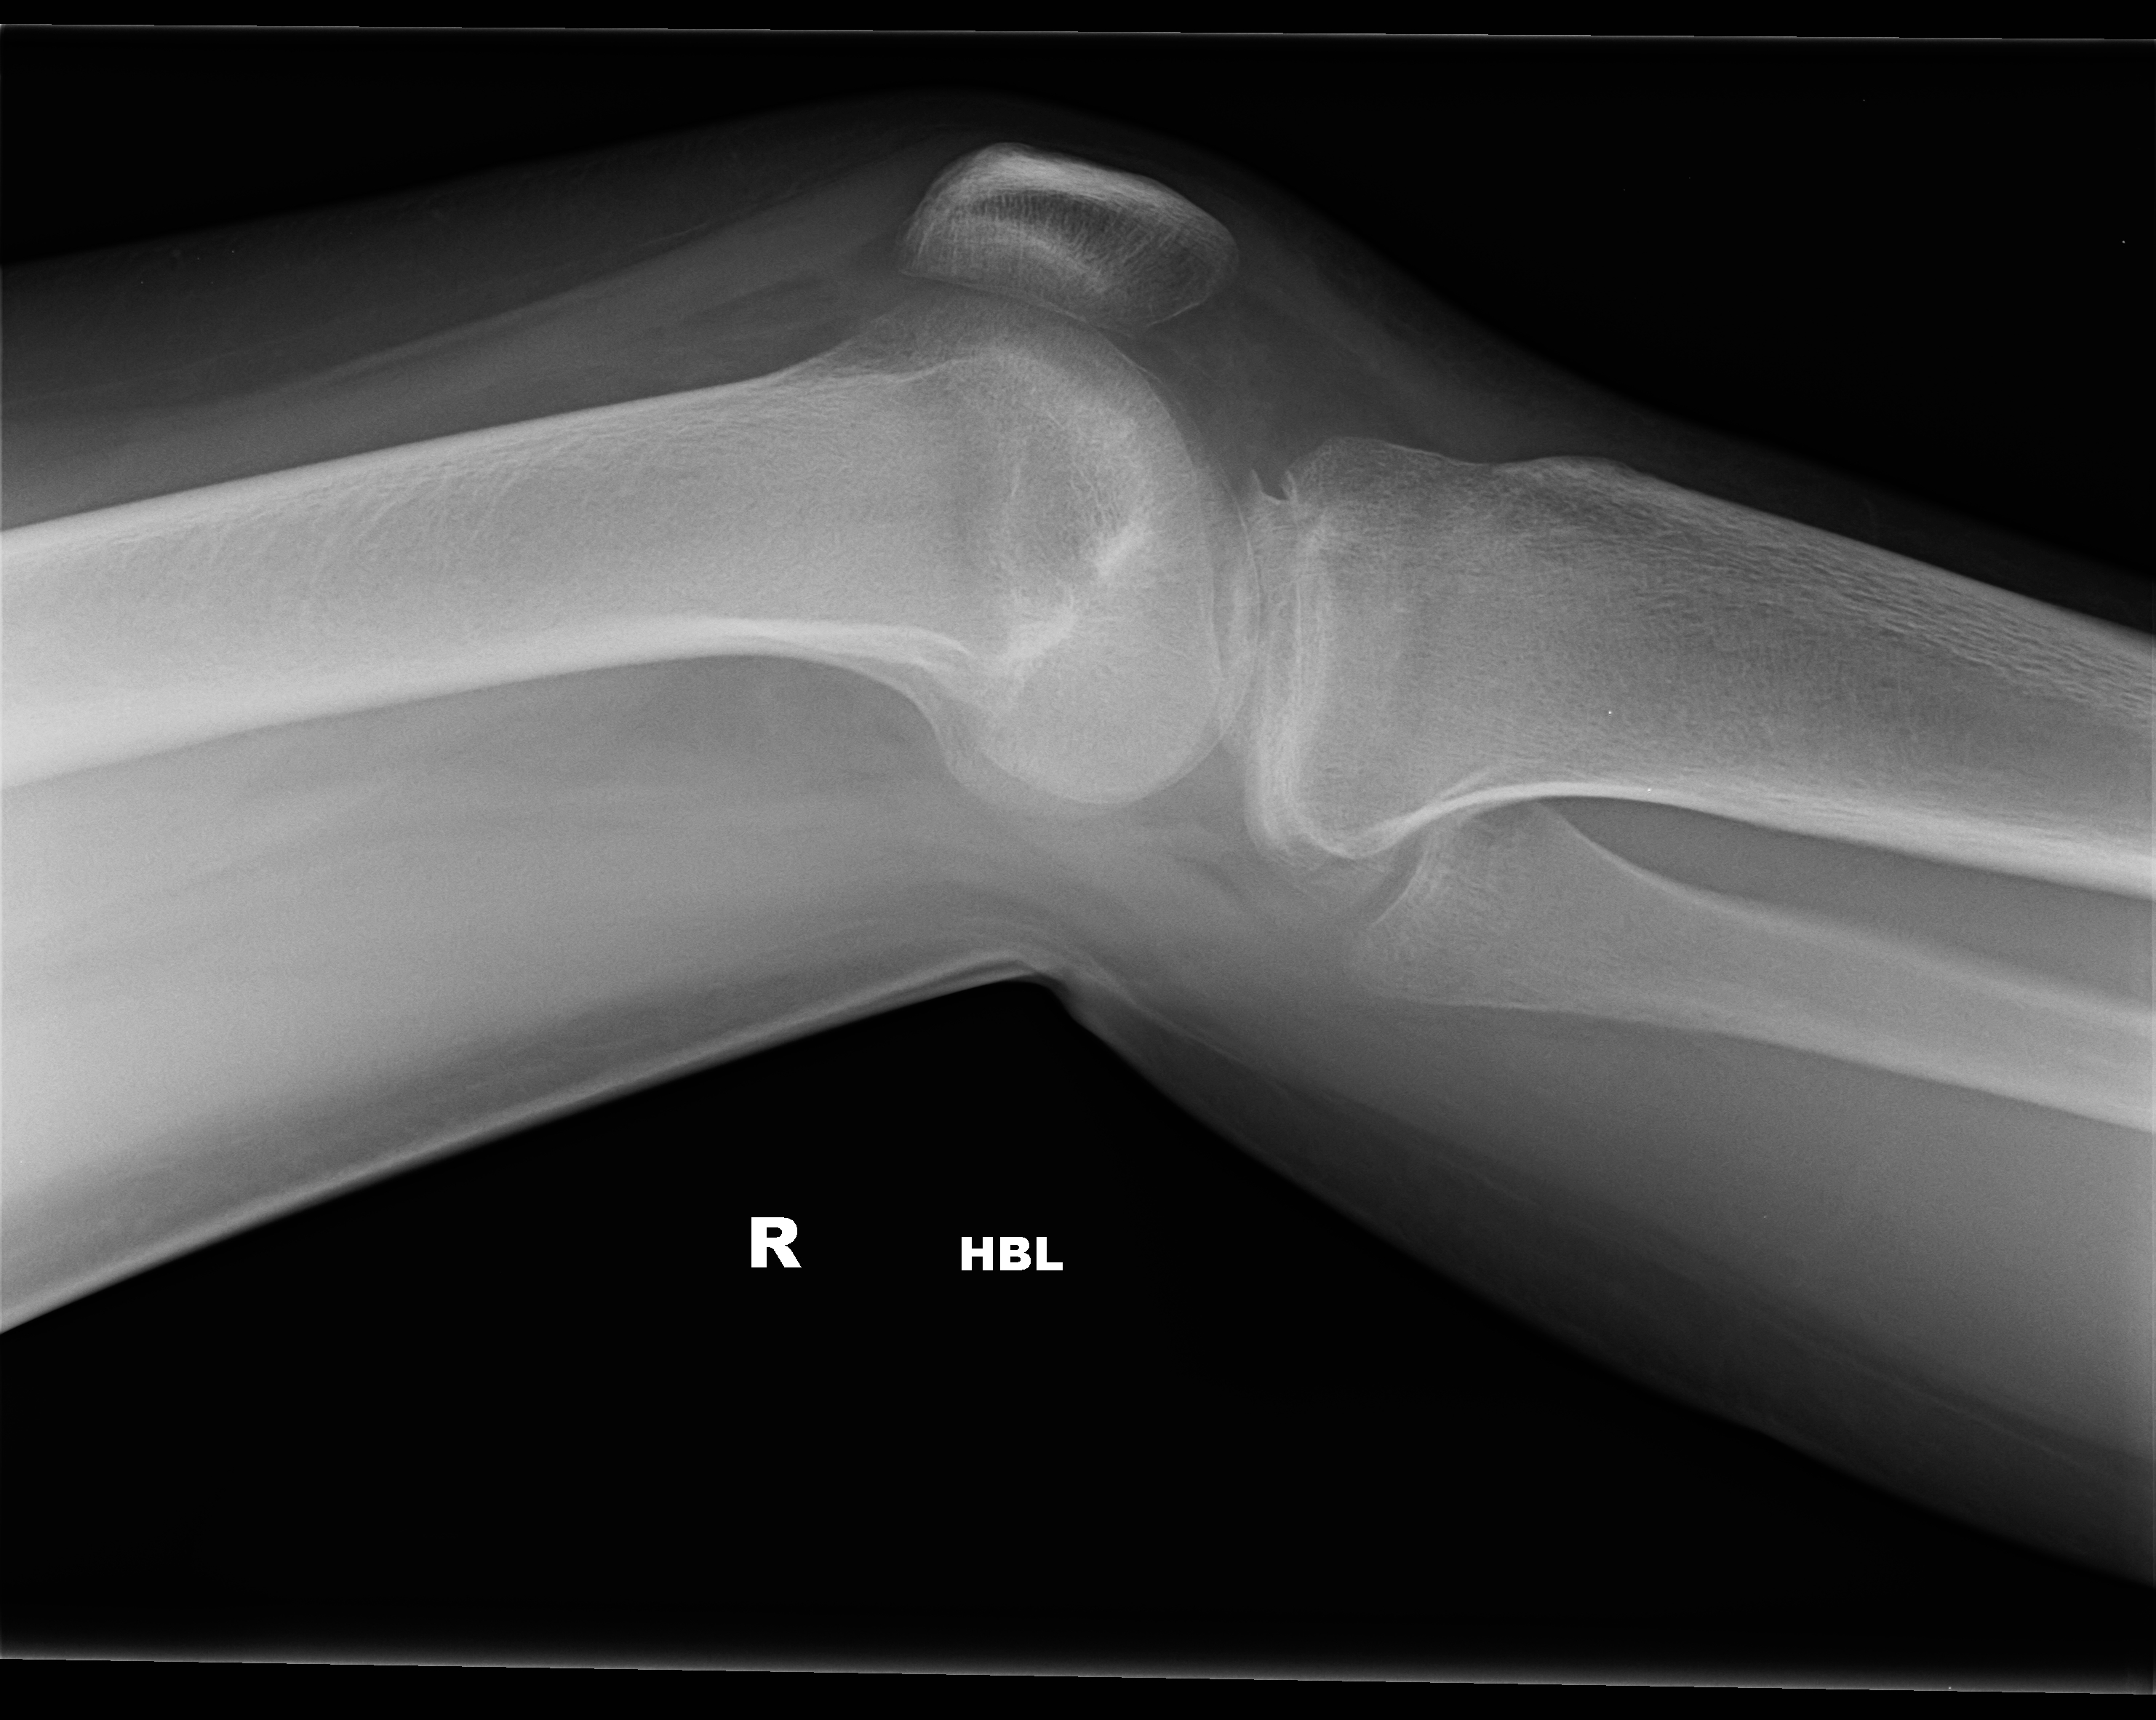

| 3 |

Abnormal fr rad head |

Abnormal Left radial head fracture |

Correct |